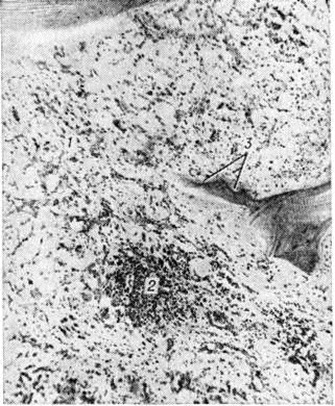

Микроскопически в костном мозге обнаруживается системное разрастание лимфоцитов. При обострении процесса наряду со зрелыми лимфоцитами выявляются пролимфоциты и лимфобласты. В костном мозге выделяют три типа инфильтрации: диффузную, диффузно-очаговую, очаговую. При первых двух типах инфильтрации расширенные полости костного мозга содержат значительное количество лимфоцитов, диффузно рассеянных в ткани или образующих наряду с этим компактные скопления (диффузно-очаговый тип). В отличие от других форм Лейкозы даже при массивной инфильтрации в костном мозге сохраняются небольшие очаги нормального кроветворения, не исчезают полностью жировые клетки. Для хронический лимфолейкоза характерно резкое рассасывание костной ткани и отсутствие признаков её новообразования. Данные прижизненного гистологический исследования костного мозга показывают, что очаговый тип инфильтрации наблюдается в ранние стадии заболевания. В отличие от лимфоидных узелков, выявляемых в норме в костном мозге, а также от реактивной нодулярной лимфоидной гиперплазии, сопутствующей ряду заболеваний, при хронический лимфолейкозе очаговые скопления лимфоцитов характеризуются довольно крупными размерами, лишены чётких границ, имеют тенденцию к слиянию, содержат наряду со зрелыми лимфоцитами пролимфоциты и лимфобласты. Разграничение этих изменений с метастазами в костный мозг лимфоцитарной лимфосаркомы ввиду сходности морфологический картины основывается на особенностях клинические, проявлений заболевания. При развёрнутой картине хронический лимфолейкоза в лимфатических, узлах обнаруживается диффузная инфильтрация ткани лимфоцитами с полным стиранием рисунка, которая может проникать через капсулу в окружающую жировую клетчатку. В селезёнке в некоторых случаях видны резко увеличенные в размерах фолликулы без центров размножения, сливающиеся друг с другом, однако чаще имеется полное стирание рисунка вследствие диффузной инфильтрации ткани лимфоцитами. Нередко встречаются поля склероза. В печени обширные скопления лимфатических, клеток располагаются главным образом в области портальных полей (рисунок 7), но могут встречаться и в синусоидных капиллярах. В зонах инфильтрации нередко имеет место разрастание аргирофильных и коллагеновых волокон. Часто наблюдается расширение желчных капилляров и застой желчи, дистрофия, частичный некробиоз и некроз гепатоцитов. В лёгких разрастания локализуются в стенках бронхов, что приводит к нарушению их дренажной функции и способствует развитию пневмоний. Могут наблюдаться участки массивной лейкозной инфильтрации ткани лёгкого. При микроскопии гнездные скопления лимфоцитов нередко обнаруживаются в строме почек, оболочках и мышце сердца, половых железах, жировой клетчатке и так далее. Очень редко встречается специфическая инфильтрация оболочек и вещества головного мозга. Частой находкой является скопление лимфоцитов в просветах сосудов различных органов, особенно при значительном лейкоцитозе. В отдельных случаях при обострении хронический лимфолейкоза возникают массивные опухолевые разрастания, исходящие главным образом из лимфатических, узлов. Опухолевые массы состоят из крупных недифференцированных клеток с уродливыми ядрами, нередко в них обнаруживаются участки некроза, кровоизлияния. Характерен резко выраженный инфильтрирующий рост.